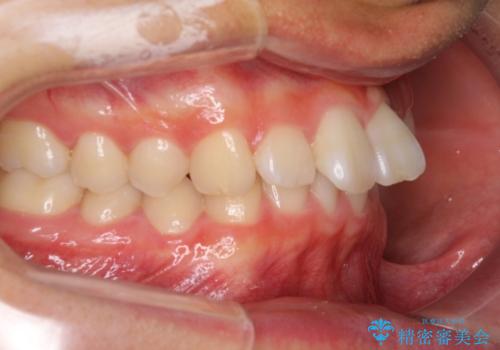

深い咬み合わせとデコボコ ワイヤー矯正で短期治療

- 前歯のデコボコを改善したいとのことで来院された患者様です。

マウスピース矯正の自己管理が面倒とのことで、ワイヤー矯正により治療を行うこととしました。

インビザラインでの治療も可能でしたが、深い咬み合わせと奥歯の咬み合わせを改善するにあたり、ワイヤー矯正の方が治療期間を短縮できると判断し、ワイヤー矯正をお勧めしました。

結果として、1年かからずに奥歯の咬み合わせを改善することができました。